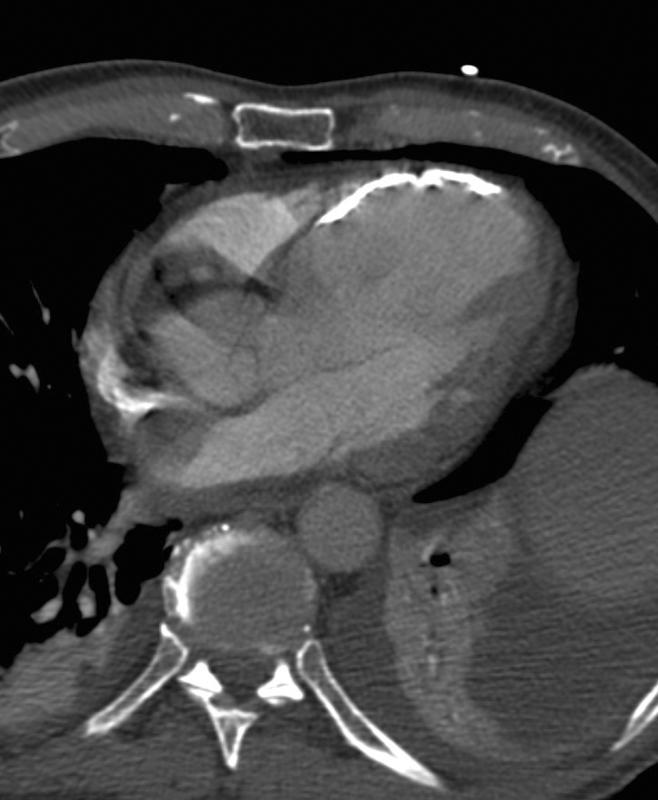

LV ant wall calcif